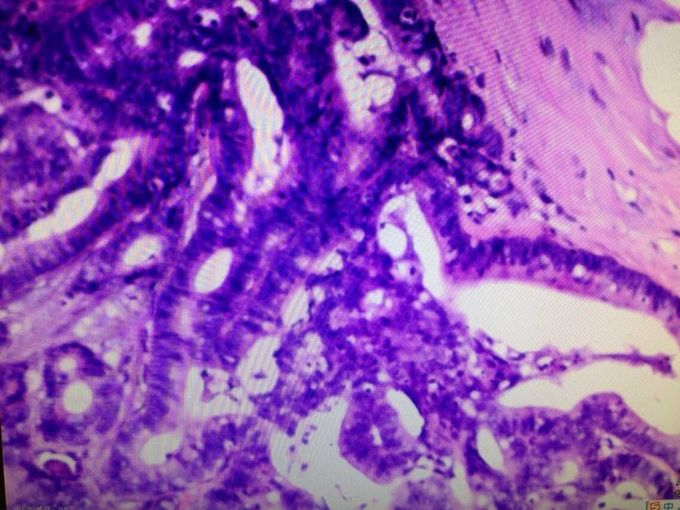

石蜡切片报告:(膀胱前顶壁)送检组织一块,其内见粘膜组织,粘膜中央见肿物一个,体积5x4x4cm,肿物侵犯粘膜下脂肪组织,脂肪相邻处见皮肤组织一块,体积3x2x0.5cm。镜下:(膀胱前顶壁)中分化粘液腺癌,浸润膀胱壁全层达浆膜外脂肪组织,另见小块皮肤组织,未见癌侵犯。局部区域可见腺癌与膀胱尿路上皮有过渡,考虑为膀胱来源。 出院后专科门诊定期复查膀胱镜:术后前两年,每3月复查一次;第3-4年每6个月复查一次;第5年以后每年复查一次。若复查结果异常,泌尿外科就诊。行膀胱灌注治疗:法码新 50mg/50ml 膀胱灌注,每周1次,共8次;后改为每月1次,共10次;总疗程1年。